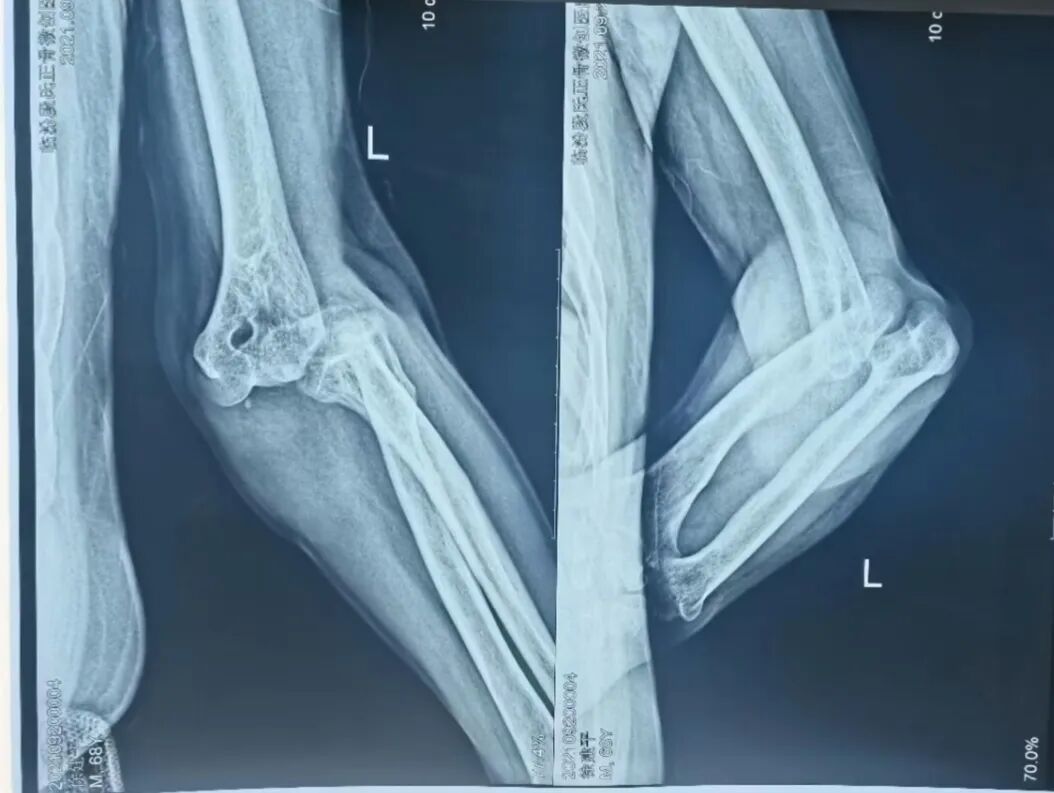

(肘关节大脱位)

(传统手法复位)